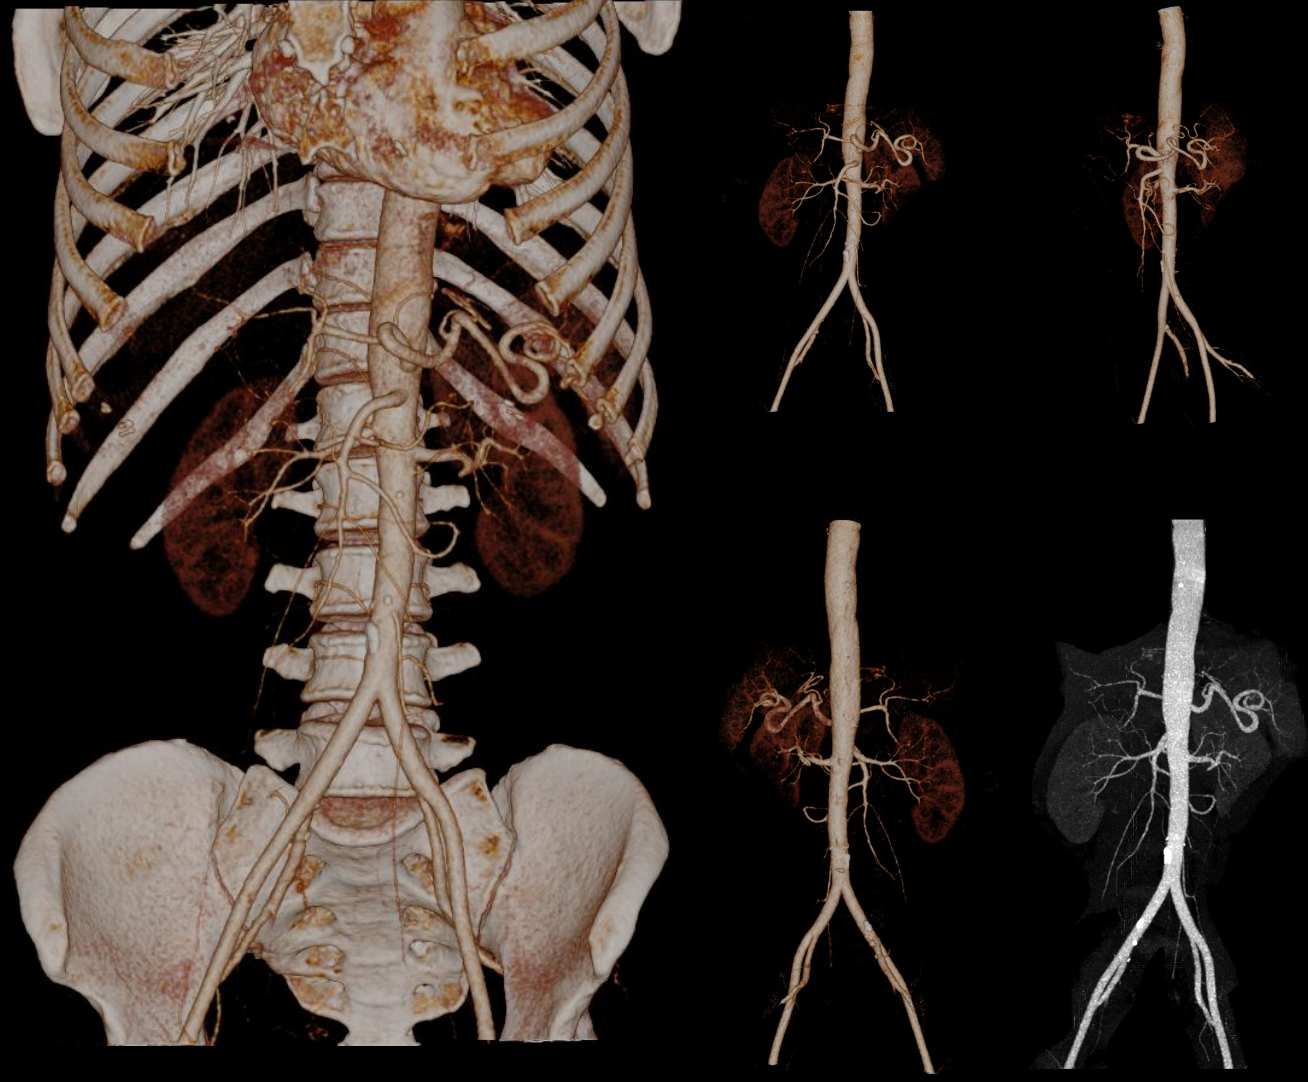

- Giải pháp chẩn đoán hình ảnh mô mềm tiên tiến cho khảo sát ổ bụng

- Tối ưu chất lượng hình ảnh chẩn đoán và giảm phơi nhiễm bức xạ

- Hỗ trợ đánh giá an toàn cho bệnh nhân

- Đảm bảo chất lượng hình ảnh chẩn đoán cao